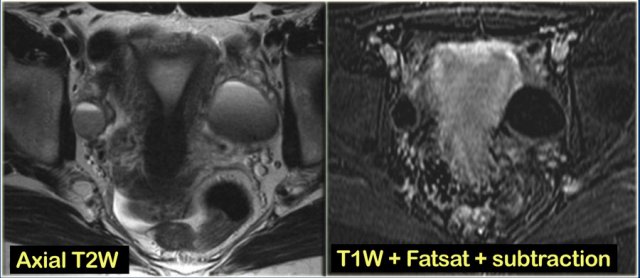

Hemorrhagic ovarian cyst in both right and left ovary Hemorrhagic ovarian cyst in both right and left ovary

The ultrasound images show the right and left ovary: on both sides there is what appears to be a solid lesion.

There is however good through transmission, which indicates that we are probably dealing with hemorrhagic cysts.

On Doppler US (not shown) there was no vascularity.

Continue with the MR examination.

Hemorrhagic ovarian cyst Hemorrhagic ovarian cyst

On an axial T1-weighted image both lesions are bright indicating fat, blood or high protein fluid.

Fat saturation does not suppress the signal in these lesions.

In an image with overall reasonably good fat suppression this rules out a fat-containing teratoma and confirms the suggestion of hemorrhagic fluid.

Hemorrhagic ovarian cyst. Left:image without subtraction. Right: image with subtraction. Hemorrhagic ovarian cyst. Left:image without subtraction. Right: image with subtraction.

On the axial T2-weighted image both lesions show typical 'shading'.

The gradual drop in T2 is thought to be caused by a combination of increasing viscosity and increasing concentration of protein and iron towards the dependent portion of the lesion.

There is no enhancement on the subtraction image (Post-Gd minus Pre-Gd).

Again, subtraction is useful in cases like this: Gd-induced signal increase over the already very bright pre-contrast image would be very hard to appreciate otherwise.